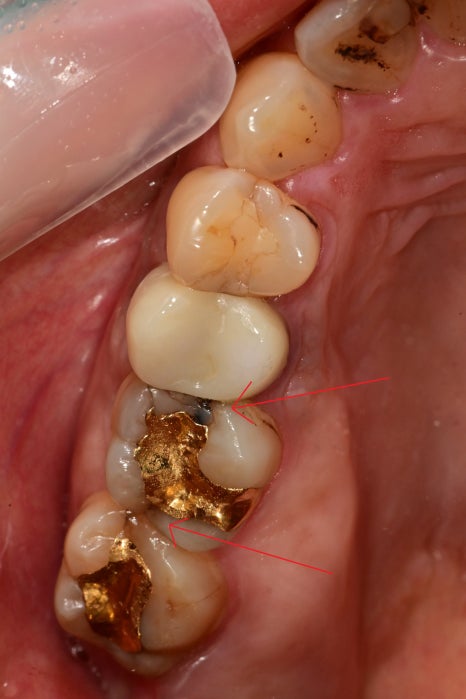

구강 내에서는 아래쪽 뿐 아니라

대합 되는 부위에서도 다발성의 크랙이 관찰되었습니다.

치아의 파절과

좌우로 진행된 금간 부위 하방으로

2차 우식까지 진행되었습니다.